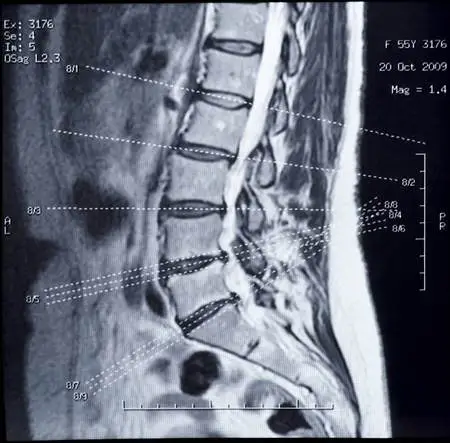

Diagnosing Your Herniated Disc

What is the best way to diagnose your disc herniation? Discography seems to be the gold standard according to some authorities but it is controversial. First, your doctor has to inject the disc with contrast dye which creates a hole in the disc. There is no way to inject the contrast dye without creating a hole.

However, to some, it remains the gold standard.

Mechanical assessment in the hands of a skilled clinician is superior to MRI in predicting which disc is painful and if the annulus is intact or not.

Sadly though patients are often diagnosed by MRI, many times at the insistence of the patient, without the clinician having done a thorough and competent mechanical examination. The examination is often cursory many times lacking a thorough neurological examination.

It’s really up to you as a patient to make sure that you get a thorough history and examination. If you didn’t and simply got an MRI after a cursory exam then chances are it’s diagnosis by MRI which is very common in India judging by the comments on this website but happens quite often in Western countries.